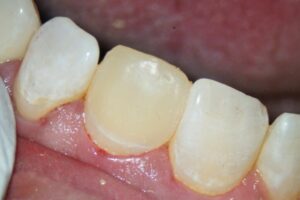

Die Therapie wurde in enger interdisziplinärer Abstimmung zwischen dem Endodontologen und dem Prothetiker geplant. Zur langfristigen Versorgung der entstandenen Lücke hatte der Stammbehandler Ans Tawel, M.Sc. eine Keramikkrone vorgesehen. Für ein dauerhaft stabiles Ergebnis war die vorherige Wurzelkanalbehandlung angeraten. Da der Zahn noch vital war, wurde von endodontischer Seite eine Single-Visit-Behandlung geplant. Im Anschluss hatte der Stammbehandler als Provisorium einen adhäsiven Kompositaufbau vorgesehen. Dies sollte auch dem ästhetischen Anspruch im Frontzahnbereich gerecht werden.

Der provisorische Aufbau erfolgte durch den Endodontologen mit vorab gefertigtem Silikonschlüssel mittels Tetric Flow und Ceram A3,5 als Abschluss der Single-Visit-Behandlung. Die endgültige Krone konnte am 12. Juni 2025 eingegliedert werden.

Insgesamt ist die dargestellte Lösung weniger invasiv und damit patientenorientierter. Eine alternative Extraktion mit Implantatversorgung wäre aufgrund des nötigen Weichgewebsmanagements deutlich anspruchsvoller gewesen, insbesondere aufgrund der bestehenden Vorerkrankung. Nach dem effektiven Verschluss des Wurzelkanals war eine sofortige Restauration möglich, was auch der Ästhetik dient.

Die Vorteile der aufgezeigten Behandlungsstrategie liegen nicht nur in der Risikominimierung für den Patienten, sondern auch in der nahtlosen Verzahnung mit der prothetischen Versorgung: ein Termin weniger, keine erneute Anästhesie, kein Risiko einer bakteriellen Rekontamination. Somit eine interdisziplinäre Therapie, die funktionell, restaurativ und ästhetisch überzeugt. Der Patient konnte in weniger als zwei Monaten vollständig ästhetisch versorgt werden.